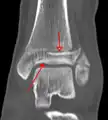

A triplane fracture of the ankle as seen on CT

- Triplane fractures are a special type of fracture that involves the immature skeleton. It has a coronal plane in the metaphysis, an axial plane in the physis, and a sagittal plane in the epiphysis.[15]